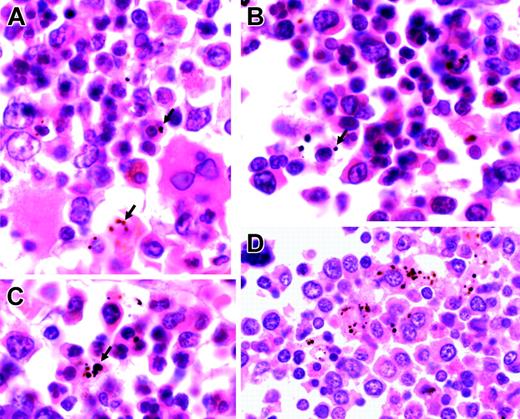

We examined 17 sections of postmortem bone marrow trephines from Malawian children who had died with malaria. All children with patent parasitemia had plentiful pigmented myeloid and erythroid cells (Figure 5; Table 5). The numbers of pigmented erythroid and nonerythroid cells per high-power field were associated with each other (r = 0.60, P = .01), and both were associated with the number of abnormal (bi-, multi-, or irregularly nucleated) erythroid precursors (erythroid: r = 0.62 and P < .008; and nonerythroid: r = 0.54 and P < .02). The number of normal erythroid cells was associated with hematocrit (r = 0.50, P = .04).

Representative sections of bone marrow from children with severe malarial anemia. (A-C) Highly abnormal erythropoiesis (irregular, bi-, and multinucleated erythroid cells) in association with Hz (arrows). (D) Hz predominantly inside myeloid cells (hematoxylin and eosin staining; original magnification, × 1000). Cells were viewed with a Nikon Eclipse E600 microscope equipped with a Nikon 100 ×/1.40 numeric aperture oil-immersion objective lens (Nikon, Surrey, United Kingdom) and a Zeiss Axiocam (Zeiss, Göttingen, Germany). Axiovision 3 software (Zeiss) was used to acquire images, and ImageJ software (http://rsb.info.nih.gov/ij) was used to process them.

The bone marrow sections from children who died with severe malaria show gross dyserythropoiesis. In these sections, we found a significant association between the quantity of Hz (located in erythroid precursors and myeloid cells—mainly macrophages) and the proportion of erythroid cells that was abnormal. These findings are consistent with a direct inhibitory effect of Hz on erythropoiesis.